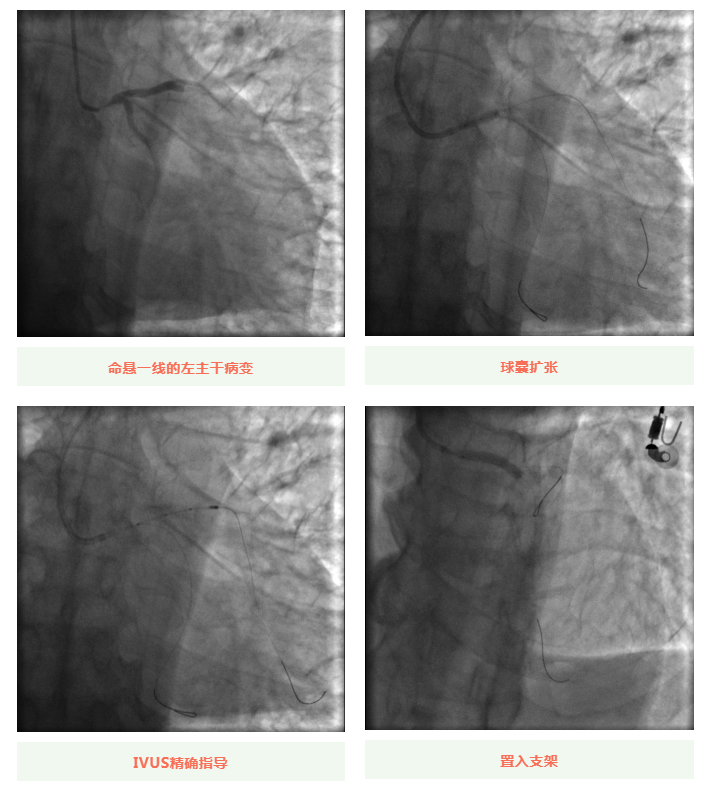

心血管內(nèi)科副主任徐先進(jìn)在主任助理農(nóng)彥林和主任汪念東的配合下行冠狀動(dòng)脈造影,結(jié)果如術(shù)前判斷一致,左主干重度狹窄,患者命懸一線。對(duì)團(tuán)隊(duì)緊急處置非常信任的李阿姨,毫無(wú)疑慮地聽(tīng)取了術(shù)者的建議,同意在血管內(nèi)超聲(IVUS)的精準(zhǔn)指導(dǎo)下,在患者左主干內(nèi)植入一枚支架,成功拯救了患者的生命。